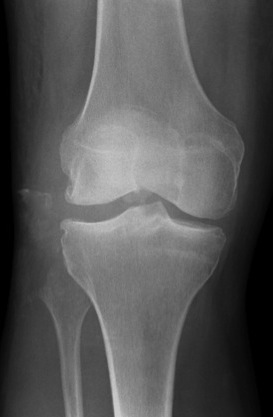

Fibular head avulsion

Fibula head avulsion and medial tibial plateau fracture